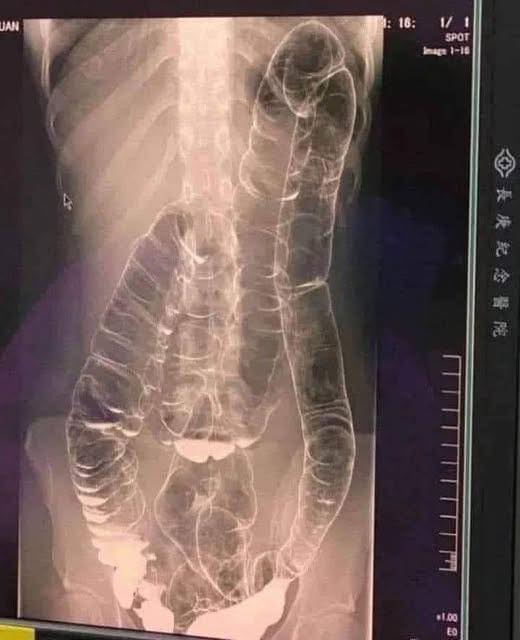

Imaginez rester plus de deux semaines sans évacuer… C'est ce qui est arrivé à une jeune femme dont le côlon s'est finalement dilaté à force d'accumulation.

- Distension du côlon : il perd son élasticité et devient de moins en moins efficace.